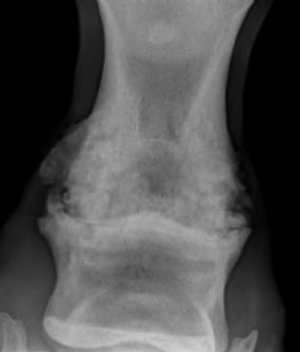

如果需要确诊是否的了关节炎,可不容易。不想马类疱疹病毒的确诊一样,可以通过血液检查得出,方便又快捷;想要判断马儿是否得了关节炎,需要给马儿麻醉并且让他们接受x光射线。

我们可以看一下这张x光。图里的马儿就有着严重的关节炎,可以看到图里的马儿关节处都有斑驳,而不是光滑的。如果这只可怜的马儿想要接受进一步治疗,只能尝试动手术,采用关节固定术(surgical arthrodesis)。关节处的骨头增生和碎片都需要通过关节内窥镜手术(arthroscopy)取出,之后才可以接受更进一步治疗。